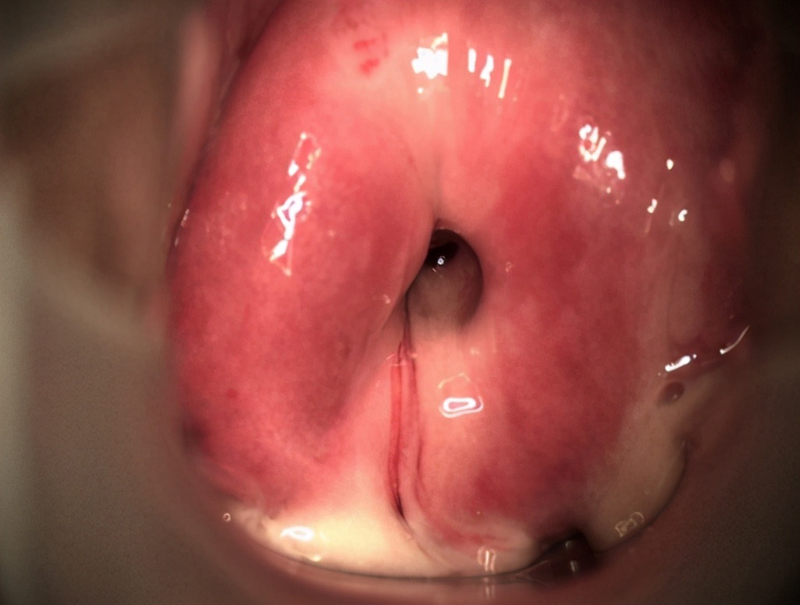

Thăm khám lâm sàng: Bác sĩ sử dụng mỏ vịt (dụng cụ khám âm đạo chuyên dụng) để đưa vào vùng kín và kiểm tra âm đạo, cổ tử cung, buồng tử cung. Hầu hết sẽ quan sát thấy được những dịch trắng bị ứ đọng tại thành tử cung, có thể màu vàng hoặc xanh. Ngoài ra, niêm mạc tử cung sẽ bị lộ ra ngoài tạo thành các lộ tuyến, gây phù nề niêm mạc và dễ bị chảy máu.